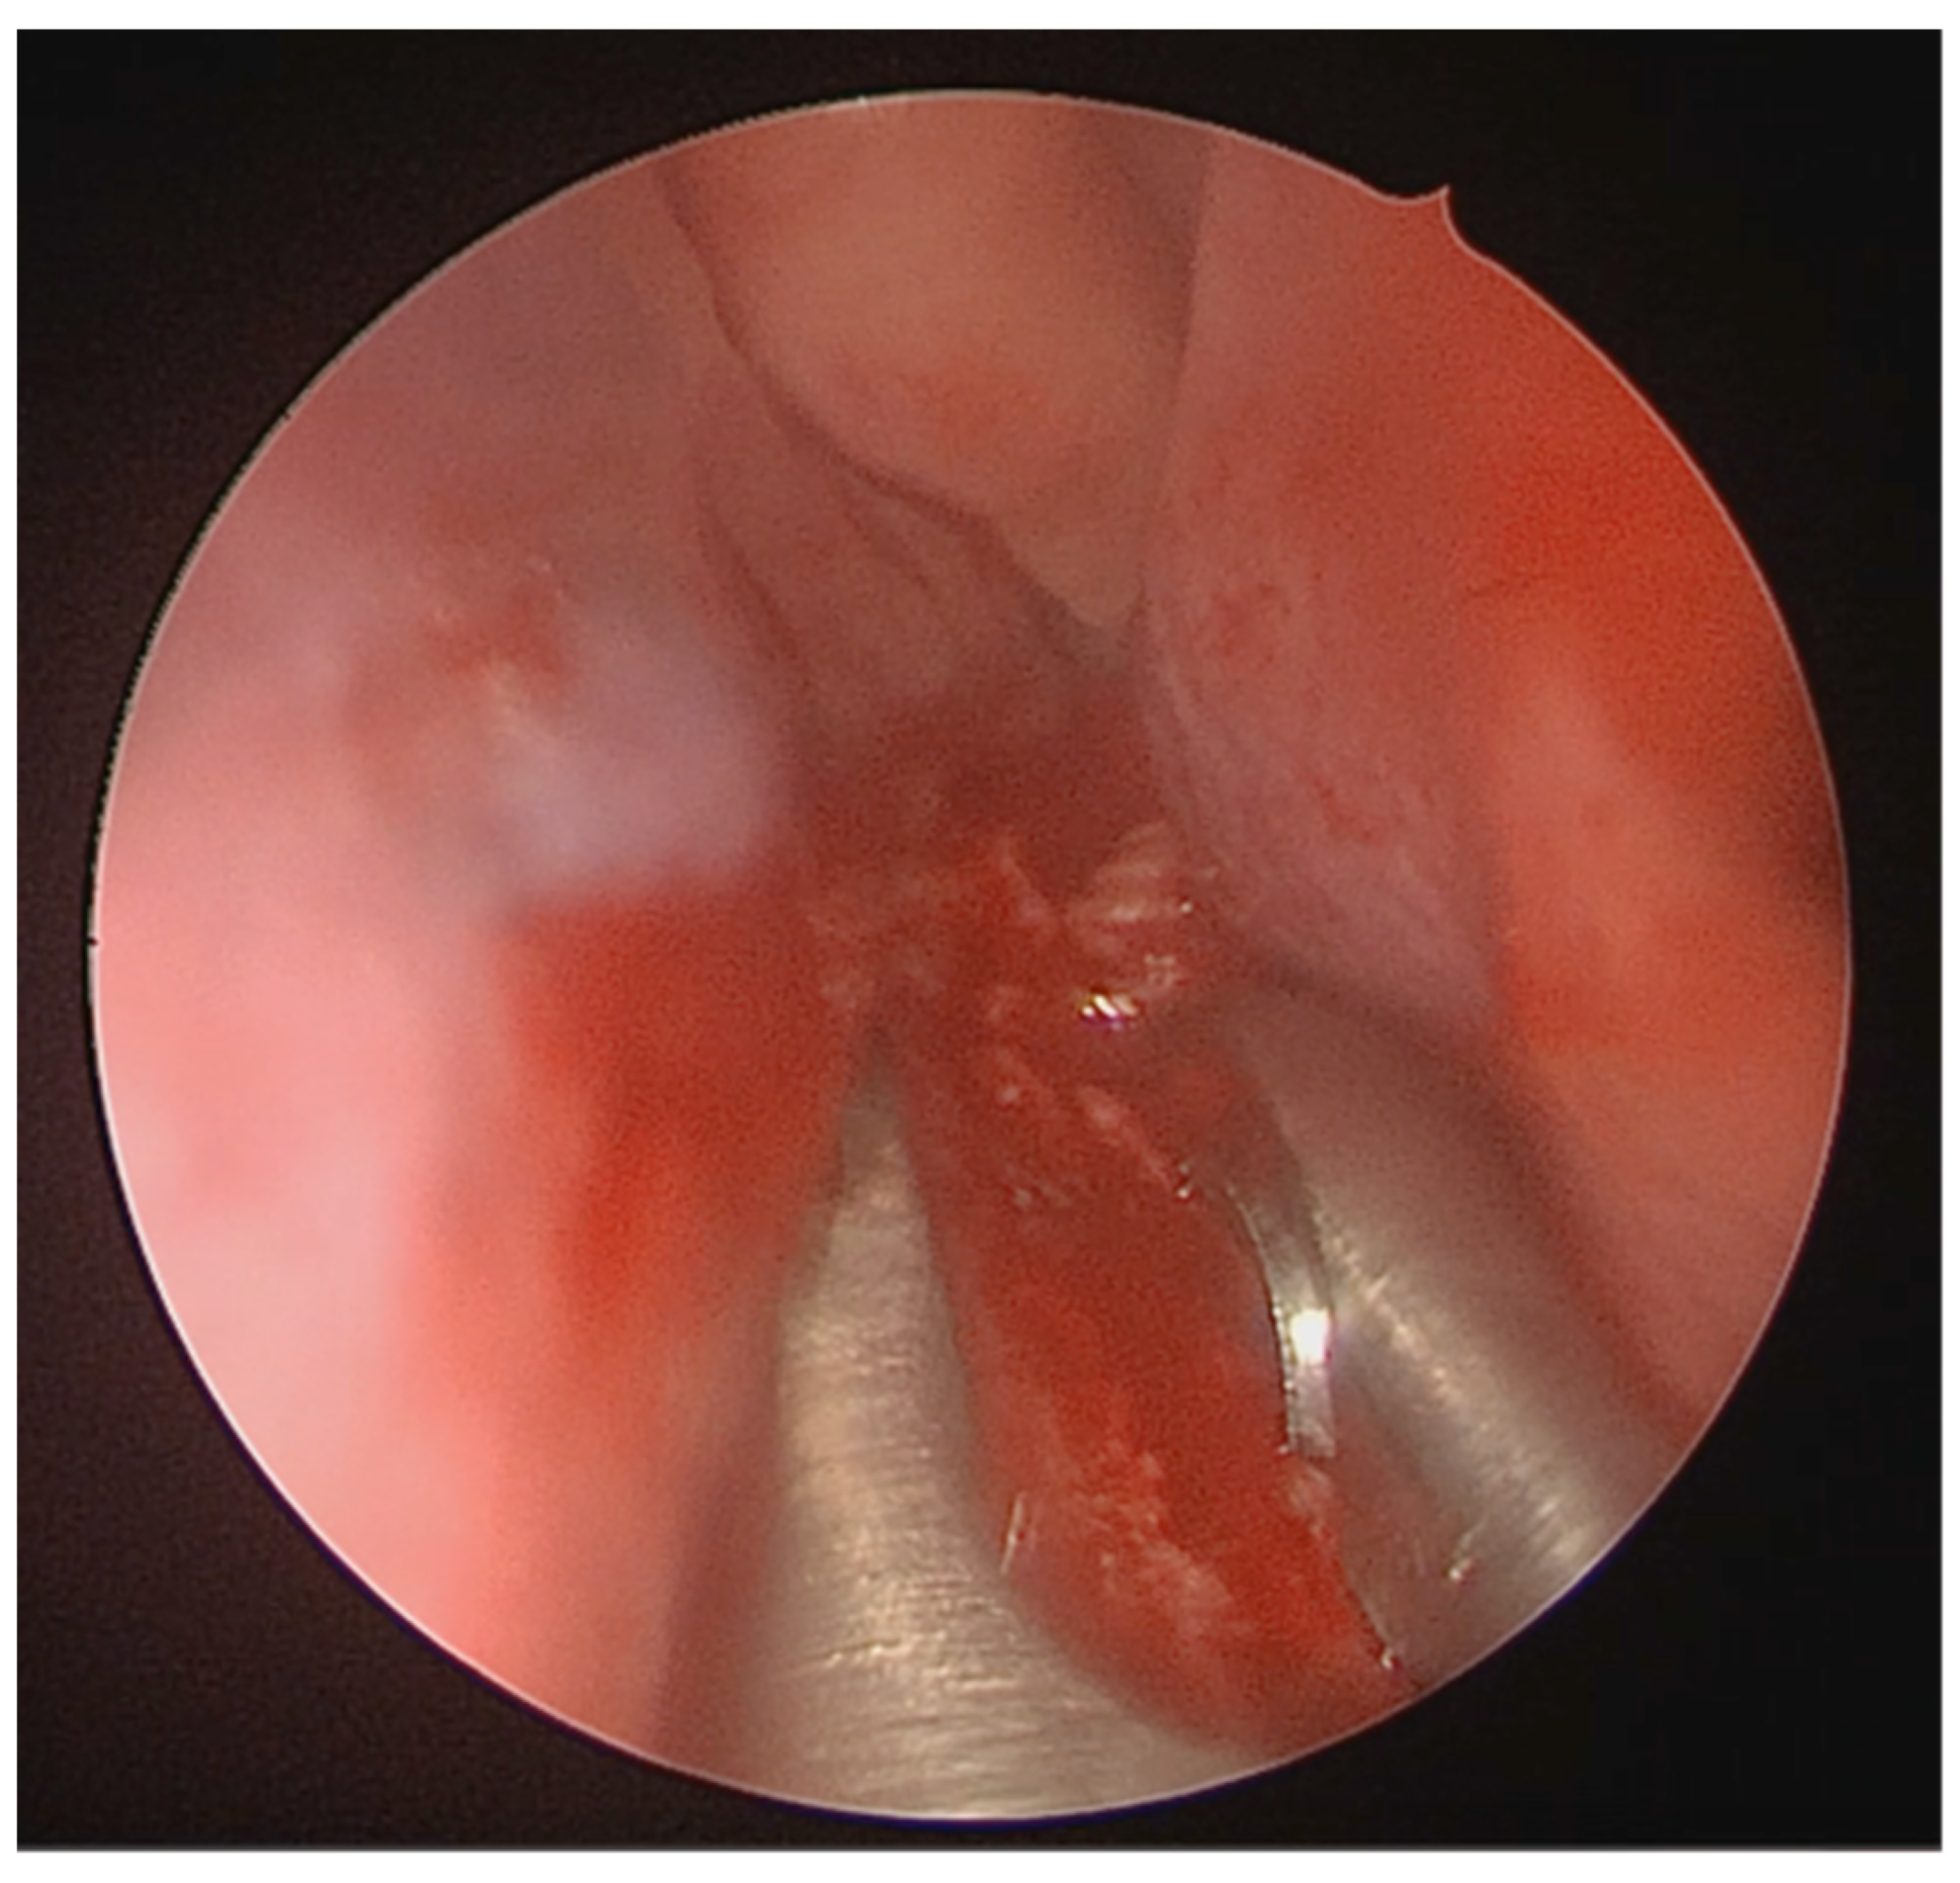

Under endoscopic visualization using a 0° endoscope, the following procedural steps were performed: For most septal deviations, standard Killian or hemitransfixion incisions were utilized (Figure 2). For Mladina types 5 and 6 deformities (corresponding to Cottle’s areas IV and V), a horizontal hemitransfixion incision was placed parallel to the nasal floor at the apex of the septal spur to adequately expose the most deviated segment, ref. [14] whereas more posterior or isolated deformities required a more posterior incision. Following the mucosal incision, mucoperichondrial flaps were elevated with a Cottle elevator, ref. [8] with optimal visualization assisted by a suction Freer elevator. Care was taken when elevating the mucosa over spurs to prevent tears due to thinning [8].

A full-thickness vertical incision was made through the cartilage a few millimeters anterior to the point of maximal deviation, which is typically located at the junction of the quadrangular cartilage and the perpendicular plate of the ethmoid [5]. The contralateral mucoperichondrial flap is then elevated in a similar manner. Once the cartilage and bone were separated from the mucosa, the deviated segments were excised using endoscopic instruments including forceps, Brünings punches, and scissors. The deviated portions of cartilage and bone were excised sharply, and the flaps are subsequently dissected inferiorly down to the nasal floor to correct deflections of the vomer. An osteotome was then positioned at the base of the spur to excise the bony protrusion (Figure 3). Deviated bony segments from the vomer or perpendicular plate of the ethmoid were removed as needed (Figure 4). After complete removal of the spur, the mucoperichondrial flaps were restored to their native positions [15]. When flap apposition was satisfactory, suturing was not required; in such cases, the incision line could be covered with a small segment of Gelfilm. Nasal packing and splints were employed only in selected cases [4].

Figure 3. Osteotome positioned at the base of the spur.